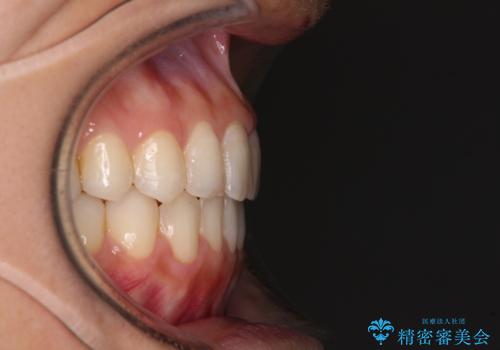

オープンバイトによる見た目を治したい インビザラインでの矯正治療

- オープンバイトのため、話しているときの見た目が気になるとのことで来院された患者様です。

下顎骨は左側にシフトしており、咬み合ったときには奥歯と前歯の一部しか接触していない状態でした。

骨格的な左右差は歯列矯正は改善できないため、上下歯列が全体的に接触することをゴールとしてインビザラインにて矯正治療を行うこととしました。

前歯のデコボコの解消と並行して上下の奥歯を圧下させるようにすることで、前歯を接触させるように計画しました。

上下の隙間に舌が入り込むことがオープンバイトの原因であったため、舌の筋肉のトレーニングも並行して行い、後戻りの抑制を図りました。